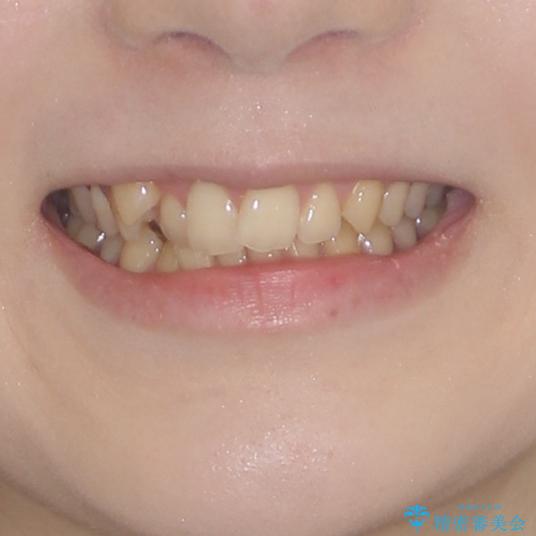

- 著しい八重歯を気にして来院された患者様です。

片側の八重歯であり上顎の正中がずれていたため、上顎左右第一小臼歯2本を抜歯して排列することとしました。